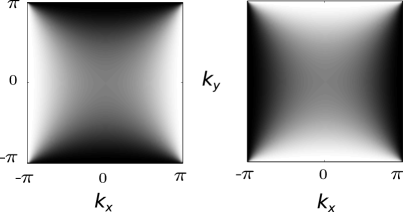

The extension to the two dimensional case is not straightforward as diagonal edges produce checkerboard-like ringing patterns, as can be observed in the phantom image in Fig. 4). Hence, it is not possible to find the optimal shift in both dimensions simultaneously. As a solution, we correct the image in both dimensions separately resulting in two one-dimensionally corrected images and . These are then combined in Fourier space to the final image via

where denotes the Fourier transform. We propose to use the ‘weighting functions’ and with a saddle-like structure in Fourier Space of the form

| (6) |

This way, the high frequency components along the direction of the correction are enhanced, while they are dampened along the non-corrected direction. Due to the normalization , artifact-free images, where , are left unchanged by Eq. 6. This ensures that minimal smoothing is introduced.